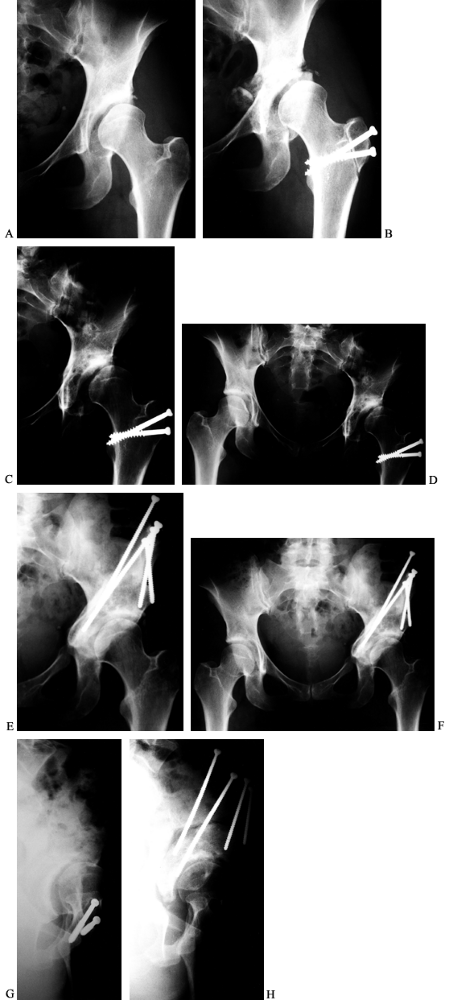

Figure 104.21. Revision of a previous, inadequate PAO. AP view of the left hip in a 31-year-old woman with dysplasia and pain (A). This AP view of the left hip shows an attempted periacetabular procedure done elsewhere (B). AP views of the hip (C) and pelvis (D)

over a year later show subluxation of the hip with poor coverage and the patient had increasing pain. A revision PAO was done. At 3 months after surgery, the patient was already walking without aids and limping only late in the day. At 8 months after surgery, it is healed (E,F). False profile view of the left hip preoperative before revision (G) and postoperative when healed (H). |

complications deserve added emphasis, since the operation is ideally

suited to young adults with early, often minimal, symptoms. Figure 104.21 shows a 31-year-old woman

who was seen after a failed attempt at a dome-type osteotomy. A PAO was

done proximal to the previous cuts with an excellent radiographic and

clinical result.